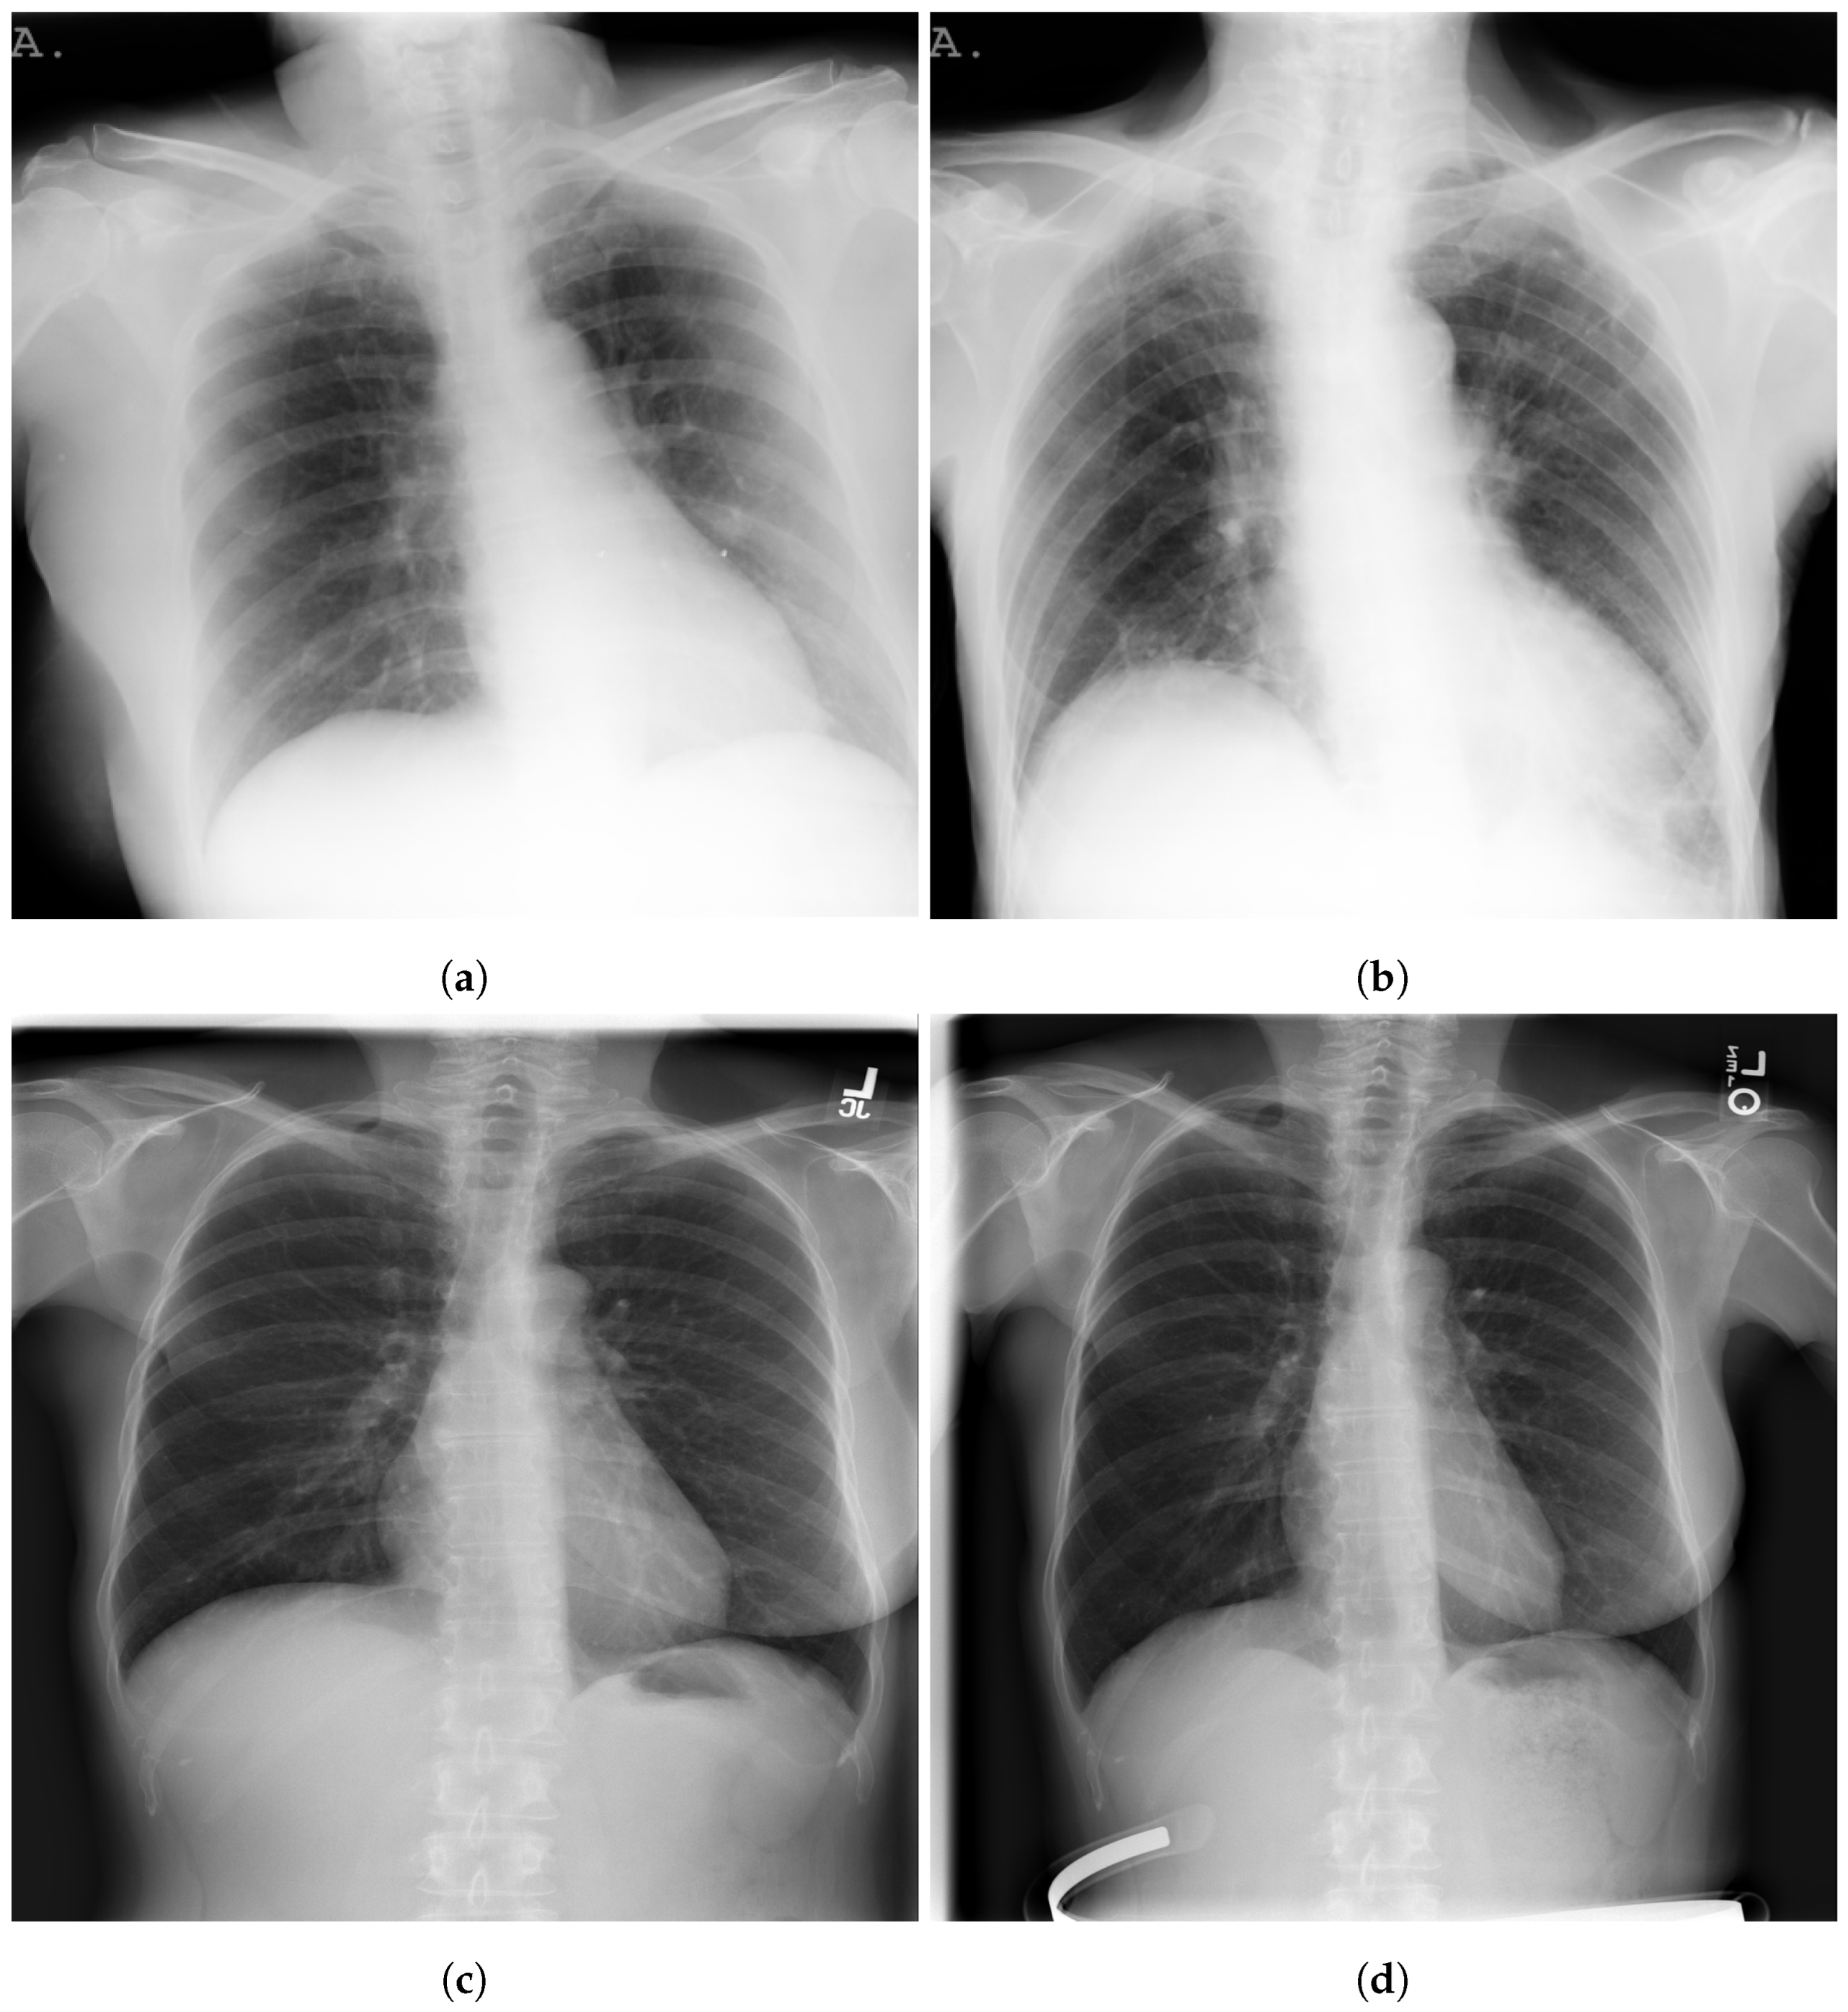

Figure 3 shows examples of SIIM-COVID-19 and RSNA CXR images.

Figure 3. Examples of BIMCV COVID+; (a,b) and NIH; (c,d) CXR images.